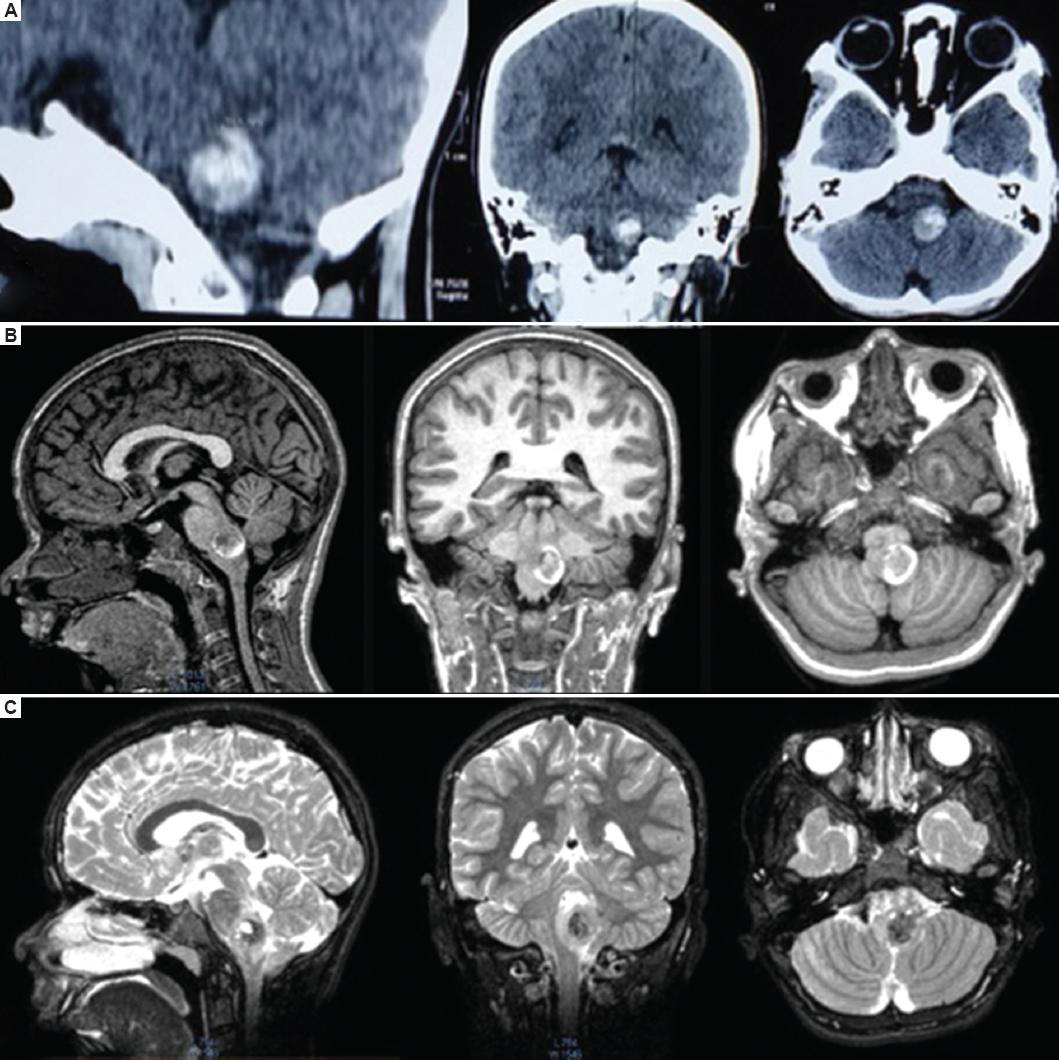

Presentamos el caso de una niña de 10 años que 7 días previos a su ingreso tuvo cefalea y pérdida transitoria del estado de consciencia con posterior recuperación, y desarrolló hemiparesia en el hemicuerpo derecho con fuerza 2/5, ataxia y afección de los nervios craneales izquierdos VI, VII, IX y X. Se le realizó una tomografía de cráneo simple y fue enviada a nuestro hospital para valoración por neurocirugía pediátrica, complementando su abordaje con RM de encéfalo y columna, que evidenció una lesión intraaxial, subpial del tallo cerebral en la unión pontobulbar izquierda, sugestiva de una MC (Fig. 1). Se realizó cirugía a los 10 días de iniciada la sintomatología. Con la paciente en decúbito prono, bajo monitorización neurofisiológica intraoperatoria y con técnicas de microcirugía, se realizó un abordaje telovelar, localizando el piso del ventrículo IV y el colículo facial izquierdo, presentando el colículo un incremento de volumen y un halo de hemosiderina. Se hizo una incisión infracolicular, obteniendo material hemático antiguo, y se identificó una MC de 7 mm que fue resecada totalmente, se corroboró la hemostasia y se cerró por planos de manera convencional (Fig. 2). La paciente fue extubada a las 72 horas. Al persistir con dificultades para la deglución, requirió una gastrostomía endoscópica. Fue egresada a su domicilio a los 7 días del posoperatorio. Se le dio seguimiento en la consulta externa, confirmando el diagnóstico de MC por histopatología. A los 4 meses logra deambular de forma independiente, con una fuerza 4/5 en el hemicuerpo derecho, resolución de la parálisis facial y capacidad de deglución, y se le retira la gastrostomía por lograr un adecuado peso para su talla y edad; aún persistía afección del VI nervio craneal izquierdo. Al año de la cirugía recupera totalmente la fuerza del hemicuerpo derecho y la función de los nervios craneales. Se realiza una RM de encéfalo de control que evidencia la ausencia de la MC (Fig. 3). La paciente no tiene antecedentes de exposición a radiación ni historia familiar de MC, y se descartó una alteración genética.

Figura 1 La tomografía computarizada simple de cráneo en cortes sagital, coronal y axial (A) evidenció una lesión hemorrágica heterogénea en la unión pontobulbar izquierda. La resonancia magnética (RM) en secuencias T1 (B) y T2 (C) en cortes sagital, coronal y axial mostró una lesión subpial a nivel pontobulbar izquierdo, con diferencia en las intensidades, sugestiva de probable malformación cavernomatosa.